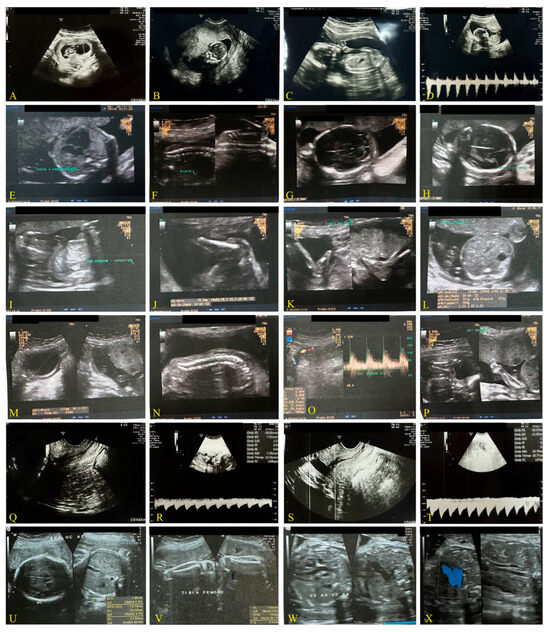

Third Case: Pandemic Period, December 2021, Delta Variant (Figure 3)

| Weeks of gestation and Ultrasound data | 20 + 2 days | 21 + 1 days | 20 + 4 days |

| Biparietal diameter (BPD) | 47 mm | 52 mm | 46.4 mm |

| Occipital-frontal diameter (OFD) | 61 mm | 67 mm | - |

| Head circumference (HC) | - | 190 mm | 178 mm |

| Abdominal circumference (AC) | 150 mm | 166 mm | 145 mm |

| Femur length (FL) | 32 mm | 36 mm | 32.3 |

| Heart rate | 151 bpm | 140 bpm | 140 bpm |

| Estimated weight | 330 g | 430 g | 320 g |

| Weeks of gestation and US data | 29 days | 28 + 1 days | 31 days |

| Biparietal diameter (BPD) | 69 mm | 72 mm | 79 mm |

| CC | 258 mm | 253 mm | 280 mm |

| AC | 246 mm | 250 mm | 273 mm |

| LF | 49 mm | 58 mm | 56 mm |

| Estimated weight | 1230 g | 1451 g | 1600 g |